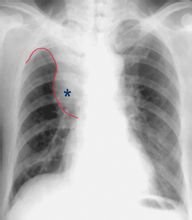

④癌瘤致支氣管阻塞則出現阻塞性肺不張。另外,癌瘤向支氣管外蔓延,形成肺門區腫塊。右上葉肺癌可出現典型的橫“S”征。

⑤癌瘤主要向支氣管管外蔓延,在肺門區形成腫塊及結節,邊緣多呈分葉狀或欠規則。右側者可示肺門角消失。

中央型肺癌中央型肺癌形成較大肺門腫塊,合併肺不張、阻塞性肺炎和/或並有縱隔直接侵犯和淋巴結轉移時,診斷並不困難。但當腫瘤較小,沿支氣管壁生長時,難與炎症性病變、結核性支氣管狹窄或其他良性腫瘤鑑別,確診需結合臨床資料和支氣管鏡檢查。